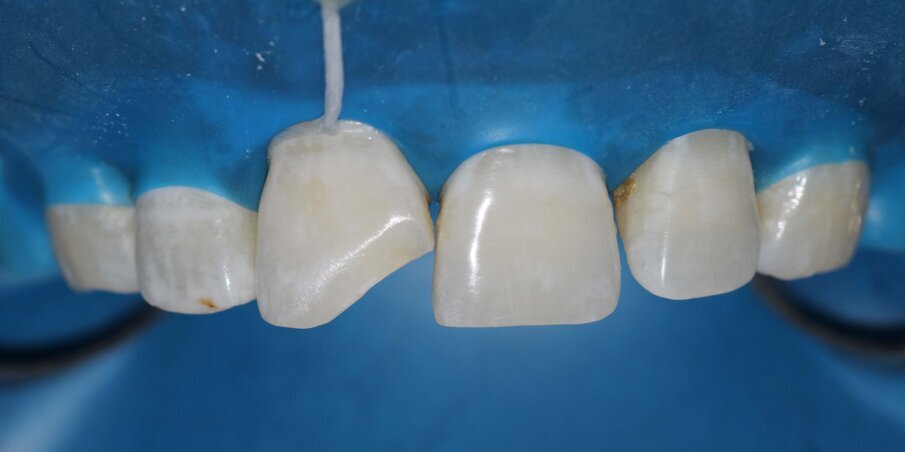

Rubber dam isolation with floss tie ligature was carried out to provide absolute isolation required for the bonding protocol. A 2mm wide bevel was given with a diamond point and finished with finishing discs involving the enamel and dentin on the buccal surface of the fractured tooth. The palatal portion of the fracture line was only smoothened to remove any overhanging enamel. The tooth was etched with 37% Phosphoric Acid (D tech) for 20 seconds. After thorough rinsing with water and light air-drying, two coats of Universal Bonding Agent (Single Bond Universal, 3M ESPE) was applied, air thinned and photocured for 20 seconds. Palatal shell was made with A2 Enamel (Filtek Z350XT) using a mylar strip and index finger held palatally for support. At this stage, the Unica Anterior Matrix (Polydentia) was adapted and secured by pulling the palatal wings and placing an interdental wedge. A2 Enamel was then applied and compacted against the matrix mesially to form the mesial surface of the restoration. Once we have an adequate ‘box’ with tight interproximal contact, it becomes relatively easy to finish the final layering. In this case, A2 Dentin, A2 Body, and A2 Enamel shades were used to complete the restoration. White opaque tints were also added before the final enamel layer to mirror the white spot characterisation of the adjacent tooth. The final enamel layer was contoured to match the mesial transitional line angle of 21 using a Mylar Pull Through method against the cured mesial wall with good contact already established with the Unica. Finishing was carried out with finishing discs (Shofu Snap-on Discs) and Soflex Spirals (3M ESPE). Polishing was done with Prisma Gloss polishing paste (Dentsply) and a rubber.

Fig 9: Unica Anterior matrix with wedge after building the palatal shell

Fig 10: Composite Build up completed and cured under Glycerin gel